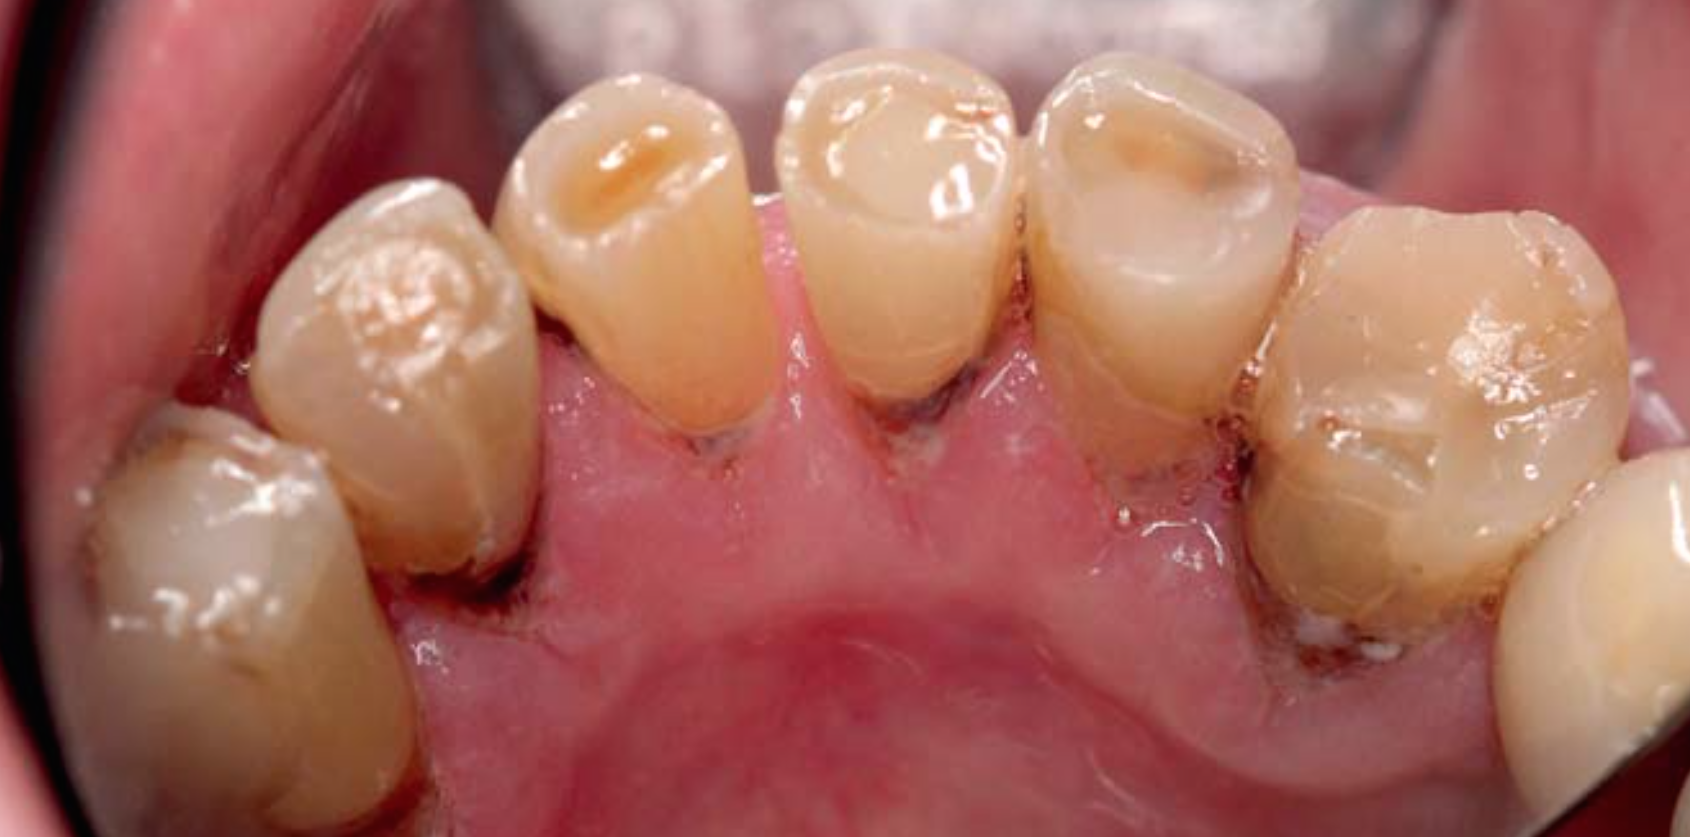

Die Prävention von Wurzelkaries ist insbesondere bei Senioren wichtig. Bei der intraoralen Untersuchung von älteren Patienten ist auf Hinweise für ein erhöhtes Kariesrisiko, z. B. Mundtrockenheit, zu achten. Das Wurzelkariesrisiko sollte durch Beeinflussung von Risikofaktoren gesenkt und das Neuauftreten oder das Voranschreiten von Wurzelkaries mit kariespräventiv wirksamen Substanzen reduziert werden.

Die Zähne von Senioren unterliegen aufgrund von altersbedingten Veränderungen einem hohen Risiko für die Entstehung von Wurzelkaries. Die restaurative Versorgung von Wurzelkaries ist oft nur eingeschränkt durchführbar: Häufig liegen die Läsionen in schwer zugänglichen Bereichen. Aufgrund von körperlichen oder geistigen Einschränkungen sind pflegebedürftige Senioren häufig nur eingeschränkt behandelbar. Daher besteht bei älteren Patienten ein hoher Bedarf an effektiven und zugleich einfach durchzuführenden Präventionsmaßnahmen. Neben der Beeinflussung von Ernährung, Mundhygiene oder Speichelfluss sollten zusätzlich kariespräventiv wirksame Substanzen eingesetzt werden. Tägliches Zähneputzen mit einer Zahnpasta mit einem Fluoridgehalt von 5.000 ppm oder die Applikation von Silberdiaminfluorid, Chlorhexidin- oder Fluoridlack scheinen die Entstehung oder das Voranschreiten von Wurzelkaries zu reduzieren. Die Evidenz zur Wirksamkeit dieser Maßnahmen basiert jedoch nur auf wenigen klinischen Untersuchungen.